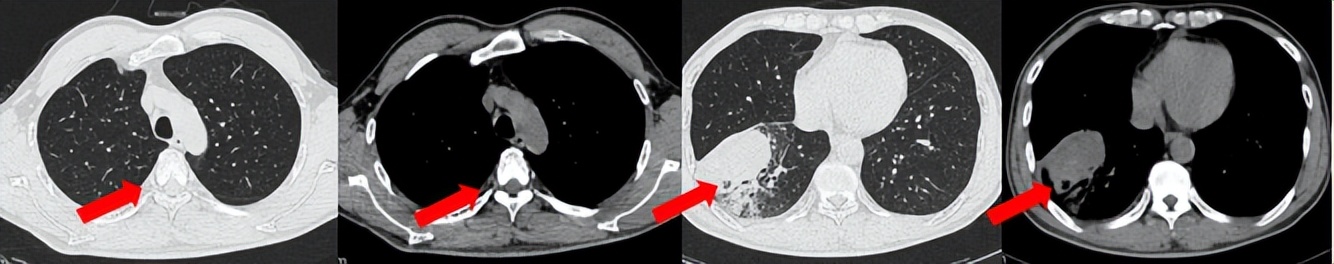

55岁男性,无吸烟史,有饮酒嗜好。2024年11月常规体检胸CT:左肺上叶占位性病变,大小约2.7×2.4cm,恶性可能大;左肺、左侧叶间胸膜及胸膜下多发微小结节,转移待除外。左侧胸腔积液,部分骨质改变。2024年12月初肺穿刺活检,病理:(肺)腺癌。NGS基因检测:CCDC6-RET(exon1-exon12)融合突变阳性(丰度:13.21%)。PD-L1表达阳性(TPS=35%,CPS=45)。

治疗经过:2025.01开始口服普拉替尼(400mg,qd)。2025.03复查胸CT:左肺上叶、右肺上叶、左肺斜裂见多发实性结节影,长径范围约3-17mm,较大者大小约17mm×12mm,位于左肺上叶下舌段,可见分叶、毛刺、胸膜凹陷、棘状突起征象。纵隔内小淋巴结。评效PR,随访中。治疗期间未出现毒性反应。

2024.12

2025.03评效PR